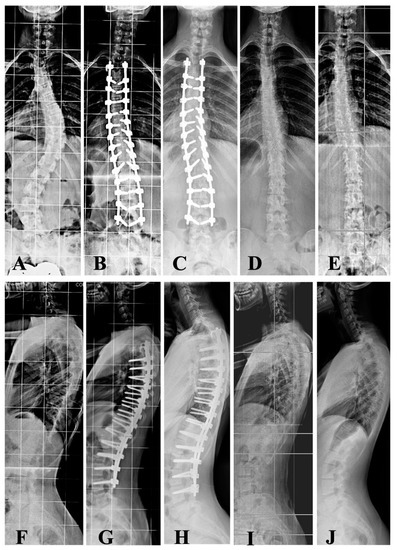

Fusionless All-Pedicle Screws for Posterior Deformity Correction in AIS Immature Patients Permit the Restoration of Normal Vertebral Morphology and Removal of the Instrumentation Once Bone Maturity Is Reached

2.3. Intervention

3.2. Radiological Outcomes

3.5. Quality of Life